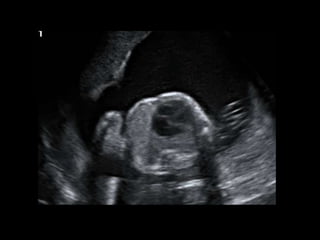

Dr. Anne Silas

HISTORY

• 40 yo female 8.5 weeks pregant

• S/P D&C for pregnancy implanted at site of

c-section scar

• 6 weeks post D&C patient presents with

heavy persistent bleeding

• For Pelvic US

• HCG = 451 mIU/mL

• What are the findings?

• What is the differential diagnosis?

• What are your recommendations?

• What is the diagnosis?

• What is the treatment?